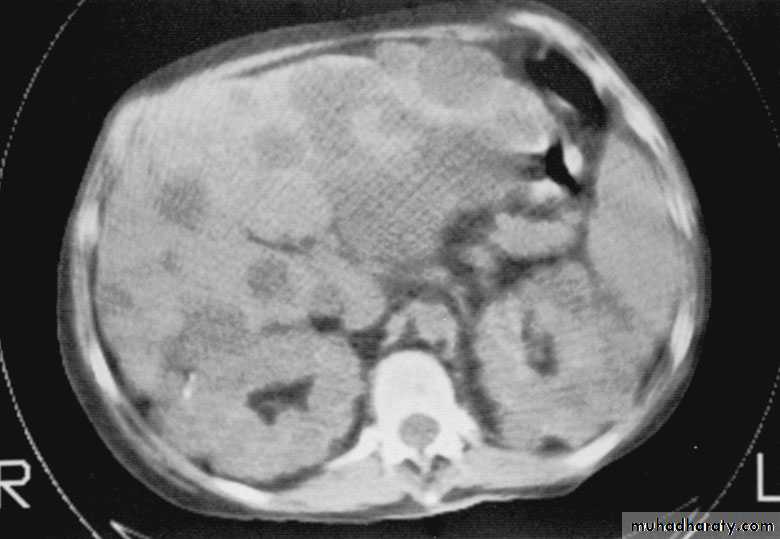

Both kidneys replaced by large no. of cysts of variable size which make the kidney of large size.

The cysts contain clear fluid but sometimes blood.

The cysts progressively increase in size causing pressure atrophy of the renal parenchyma and pressing the ureter.

U/S, IVU, CT scan, MRI